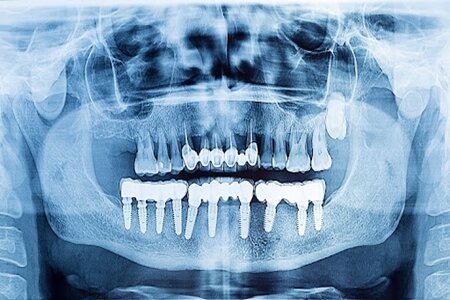

وی بیان کرد: استفاده از تکنیکهای تصویربرداری سه بعدی (CBCT) به دلیل توانایی در ارائه جزئیات دقیقتر از ساختارهای استخوانی و بافتهای نرم، نسبت به روشهای دو بعدی برتری دارد که این تکنیک امکان مشاهده لایههای مختلف و اندازهگیری دقیقتر را فراهم میکند.

نصراللهی افزود: در صورت عدم دقت در تصویربرداری، مشکلاتی نظیر جابجایی ایمپلنت، خونریزی و درد شدید بیمار ممکن است رخ دهد. بنابراین، توجه به جزییات و دقت در اندازهگیریها ضروری است.

وی ادامه داد: تکنیک CBCT به دلیل توانایی در ارائه جزییات بالاتر و دقت بیشتر در اندازهگیریهای استخوانی، به عنوان ابزاری مؤثر در طراحی درمانهای دندانپزشکی شناخته میشود.

وی ادامه داد: در فرآیند طراحی ایمپلنت، توجه به فاصله ایمپلنتها از ساختارهای حیاتی و جلوگیری از آسیب به آنها از اهمیت بالایی برخوردار است.

متخصص رادیولوژی افزود: ترکیب تصاویر مختلف برای تولید یک تصویر جامع و دقیق از ناحیه درمانی، به منظور طراحی بهتر و جلوگیری از خطاهای احتمالی، مورد تأکید قرار می گیرد.